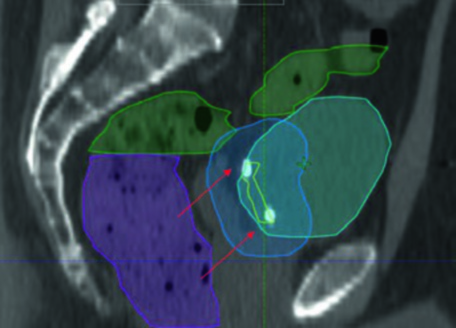

En la práctica, la planificación del boost vesical requiere marcadores fiduciales de oro implantados en la periferia del lecho de resección. Estos fiduciales permiten el registro diario con precisión submilimétrica. Observe cómo el PTV boost (azul) envuelve el lecho de TURBT (amarillo) con margen de 1 cm, mientras el recto (magenta) y el intestino (verde) se protegen mediante la conformación IMRT. Las flechas señalan los fiduciales que sirven como objetivos principales para la guía por imagen diaria.

La vista sagital confirma la importancia del margen asimétrico: superiormente, donde la variabilidad de llenado vesical es mayor, se necesita una expansión de PTV de 1,5 cm. El intestino delgado (verde) ocupa el espacio superior, reforzando la necesidad de protocolos consistentes de llenado vesical. Para comparar con la planificación de próstata — que comparte desafíos pélvicos similares — consulte nuestro artículo sobre adenocarcinoma de próstata.

El caso clínico ilustrado corresponde a un varón de 51 años con carcinoma urotelial cT2N+ localmente avanzado, con masa de 5,0 x 2,8 cm en la pared posterolateral izquierda, sometido a TURBT máxima. Las imágenes de planificación sagital y coronal demuestran cómo el PTV del SIB nodal (PTV 56,25) se superpone al campo pélvico inicial (PTV 45) sin comprometer excesivamente las estructuras adyacentes, con los fiduciales claramente visibles en el lecho de TURBT. En la fase de boost, el volumen se reduce al lecho de TURBT con margen conformado, permitiendo escalamiento seguro de dosis al tumor primario.